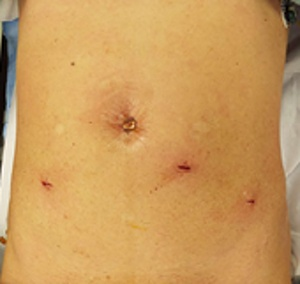

�����ɂ͂Q�`�R�̂Tmm���x�̏����Ȍ��������Ď�p�{�s���܂����A�����͎�p��A���Ԃ��o�ĂقƂ�ǖڗ����Ȃ��Ȃ�܂��B

��p�̓����ɓ��@���Ă��������A�p��Q�`�T���őމ@�ƂȂ�܂��B